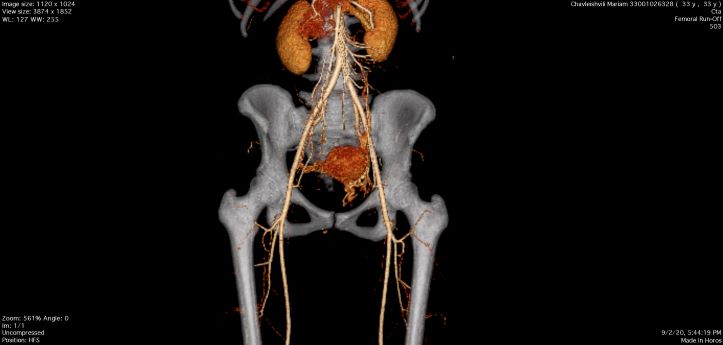

33 წლის პაციენტი მწვავე ჩივილებით (საშოდან ძლიერი სისხლდენა, ტკივილი მენჯში, ძლიერი ზოგადი სისუსტე) მოთავსდა გადაუდებელი დახმარების დეპარტამენტში, მდგომარეობა საყურადღებო იყო. მისი გადმოცემით, ბოლო რამოდენიმე თვის განმავლობაში, პერიოდულად აღენიშნებოდა საშოდან სისხლდენა კოლტებით. შეფასდა ვიტალური მაჩვენებლები, ავიყვანეთ მონიტორულ დაკვირვებაზე. ჩატარებული კვლევების საფუძველზე დაესვა ბუშტნამქერის დიაგნოზი, ჩატარდა ჰისტეროსკოპია და ენდომეტრიუმის ჰისტეროსკოპიული ამოკვეთა, თუმცა, პერიოდულად სისხლდენა კვლავ გრძელდებოდა, რის გამოც დამატებით ჩაუტარდა ქვემო კიდურების ვენების დუპლექსსკანირება და მცირე მენჯის კომპიუტერული ტომოგრაფია. კლინიკური კვლევების შედეგად გამოვლინდა საშვილოსნოს არტერიის დიდი ზომის ცრუ ანევრიზმა. შემდგომი მკურნალობის მიზნით, პაციენტი მოთავსდა საოპერაციო ბლოკში, სადაც ქირურგიულ მკურნალობას მართავდა ენდოვასკულური, სისხლძარღვთა და რეკონსტრუქციული ქირურგიის დეპარტამენტის ხელმძღვანელი გიორგი ჯინჭველაძე.

პაციენტს ჩაუტარდა მენჯის სელექტიური სუბტრაქციული ანგიოგრაფია და საშვილოსნოს არტერიის ანევრიზმის ტრანსკათეტერული არტერიული ემბოლიზაცია, რომელიც ენდოვასკულური მკურნალობის ოქროს სტანდარტია, რადგან ის არაინვაზიური, უსაფრთხო და მეტად ეფექტურია.

ოპერაციისშემდგომი მდგომარეობის შეფასების მიზნით და სისხლძარღვების სრული ოკლუზიის გამოსარიცხად პაციენტს ჩაუტარდა ემბოლიზაციის შემდგომი ანგიოგრაფიული და კომპიუტერული კვლევა, ადრეულ პოსტოპერაციულ პერიოდში და ოპერაციიდან 2 თვეში, რის შედეგადაც, პათოლოგია აღარ გამოვლინდა.